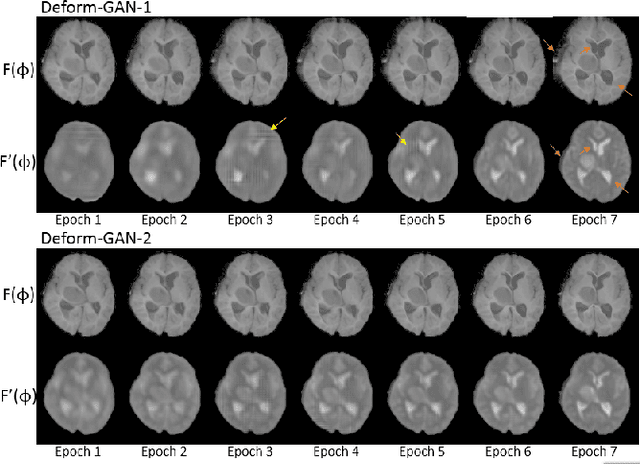

Abstract:Deformable registration is one of the most challenging task in the field of medical image analysis, especially for the alignment between different sequences and modalities. In this paper, a non-rigid registration method is proposed for 3D medical images leveraging unsupervised learning. To the best of our knowledge, this is the first attempt to introduce gradient loss into deep-learning-based registration. The proposed gradient loss is robust across sequences and modals for large deformation. Besides, adversarial learning approach is used to transfer multi-modal similarity to mono-modal similarity and improve the precision. Neither ground-truth nor manual labeling is required during training. We evaluated our network on a 3D brain registration task comprehensively. The experiments demonstrate that the proposed method can cope with the data which has non-functional intensity relations, noise and blur. Our approach outperforms other methods especially in accuracy and speed.